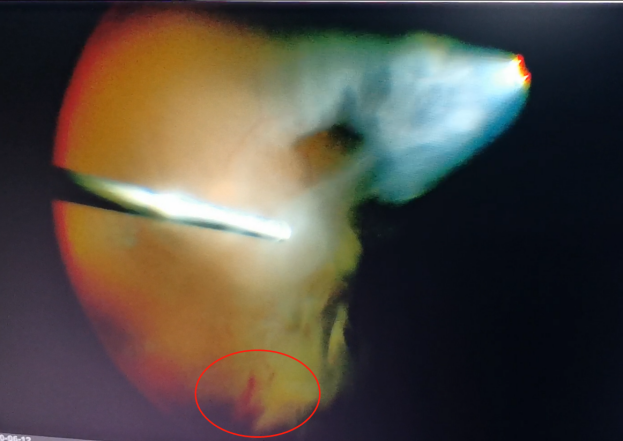

(左為玻璃體切割術(shù)中,明顯可見(jiàn)有積血;右為激光治療后的眼底)

手術(shù)中,醫(yī)生們先后為程先生行白內(nèi)障超聲乳化術(shù)及后入路玻璃體切割術(shù),并置入人工晶體。手術(shù)僅用半個(gè)小時(shí)便順利完成。